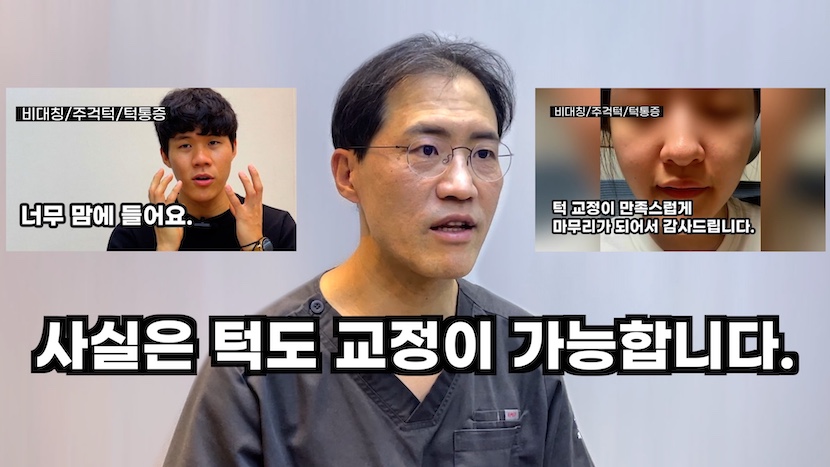

"혹시 억지로 교정하다 건강만 나빠지는 거 아니야?"

이런 생각 드시나요? 위턱과 아래턱은 관절로 연결되어 있습니다. 돌아가거나, 앞으로 나온 아래턱은 턱관절 공간을 이용해 바로잡을 수 있습니다.

턱 교정은 올바른 턱 위를 찾아주므로 심미성과 건강까지 얻는 방법입니다.